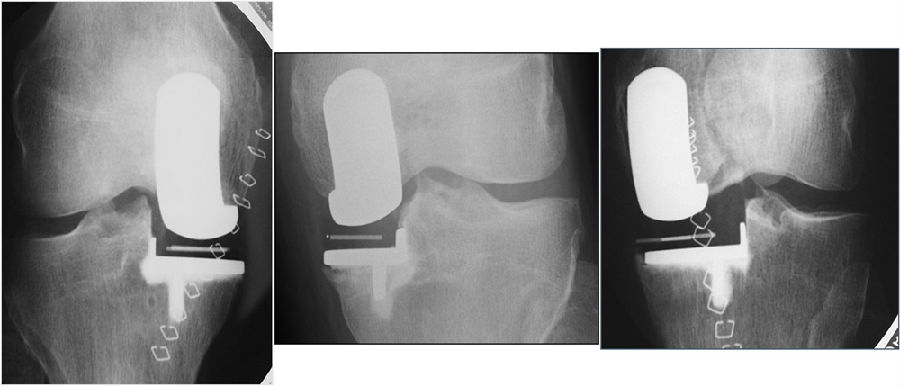

骨水泥技术:推荐初学者使用2阶段,有助于取出超出假体的骨水泥。

先固定胫骨,骨骼上的薄层骨水泥,固定胫骨假体,插入测隙器,并在45°时加压。

再固定股骨,在孔洞和假体组件中植入骨水泥,插入测隙器,并在45°时加压。